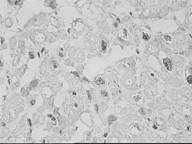

Реакция на p-53 отмечена в ядрах кардиомиоцитов, имеется небольшое фоновое окрашивание цитоплазмы, во всяком случае на рис. 1–4 хорошо видно, что интенсивность экспрессии в ядрах различна; имеются больные, у которых количество ядер с (+)-реакцией попадает в различные ранги.

Некоторое удивление вызывает тот факт, что у многих больных число окрашенных ядер превышает 50% от общего числа. Впрочем будем считать это отличительной особенностью настоящей серии исследований.

Рис.1. Положительная реакция на p–53 в немногочисленных ядрах кардиомиоцитов

Рис.2. Положительная реакция на p–53 в большей части ядер кардиомиоцитов (I группа)

Рис. 3. Положительная реакция на p–53 в большей части ядер кардиомиоцитов (II группа)